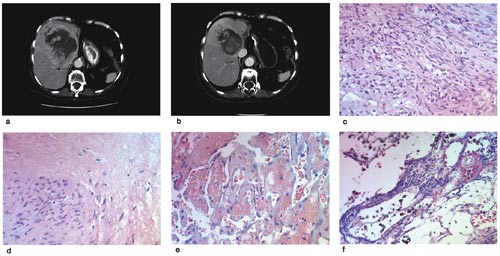

Hos pasient 1 kunne vi studere både den radiologiske og histologiske effekten av imatinibmesylat i tumorvevet (fig 1). Før behandlingsstart med imatinibmesylat viste pistolbiopsi fra levermetastasen et spolcellet, celletett tumorvev med mindre myksoide områder. Cellene viste vakuolisering, lite atypi og pleomorfi. Materialet fra leverresektatet viste tap av tumorvevet, erstattet dels av hyalint, dels av løsmasket bindevev med dilaterte kar, større nekrotiske områder og blødning (fig 1). Det ble funnet spredte, pyknotiske tumorceller og rikelig hemosiderinholdige makrofager. I mindre områder fantes rester av vitalt tumorvev med samme utseende som i pistolbiopsien tatt før behandlingsstart. Immunhistokjemisk var det sterk positivitet for Kit i begge preparatene fra levermetastasen.

Histologiske forandringer påvist i tumortomten etter behandling med imatinibmesylat hos pasient 1, et hyalint og løsmasket vev, er beskrevet tidligere (22). Hos vår pasient fant vi også vitalt tumorvev, noe som kan tilsi resistensutvikling.